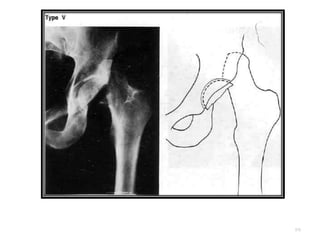

CLASIFICACION DE

THOMPSON Y EPSTEIN

• Tipo V: Luxación posterior con fractura de la cabeza

femoral.